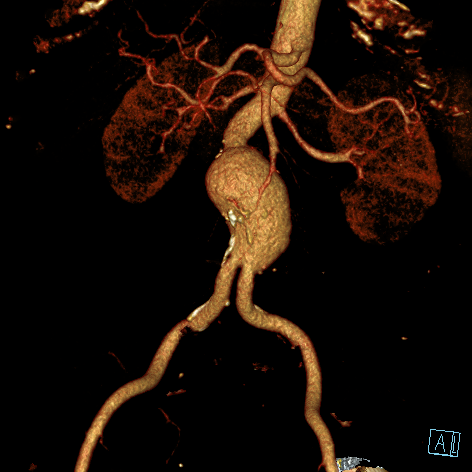

Eine Erweiterung der Bauchschlagader kann das Risiko eines Gefäßeinrisses stark erhöhen (Aneurysma). Die Radiologie bietet hier zusammen mit den Kollegen der Gefäßchirurgie ein minimal-invasives Verfahren zur Ausschaltung des Aneurysmas an. Dies geschieht mittels Stent-Prothese (endovascular aortic repair; EVAR).